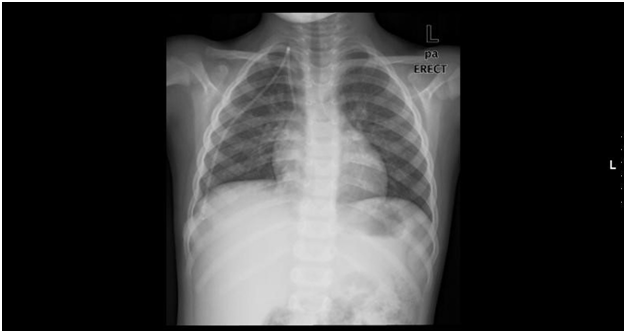

Five year old boy, a known case of acute lymphoblastic leukemia (T cell ALL) has started to receive chemotherapy using a Port-A-Cath which was inserted surgically (BARDPORT®, 10.8mm diameter, USA) (Figure 1). A chest radiograph has documented the normal position of the Catheter postoperatively (Figure 2). The patient received regular courses of chemotherapy following catheter insertion with no encountered problems.

Figure 2 Shows a normal position of the Port-A-Cath in the superior vena cava.